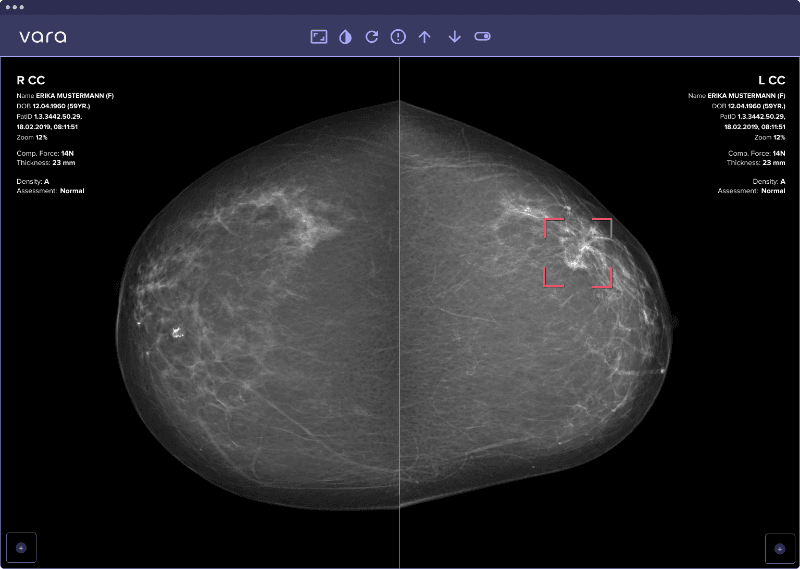

Safety net: For cases where the AI is very confident that the images are suspicious, it offers a safety net: Should the radiologist classify one of those cases as negative, the safety net triggers and points the radiologist to a specific region in the image that is suspicious to the AI. The radiologist can then reconsider the decision, potentially catching a cancer that would have otherwise been missed.

The safety net localizes where in the image a suspicious lesion is detected: